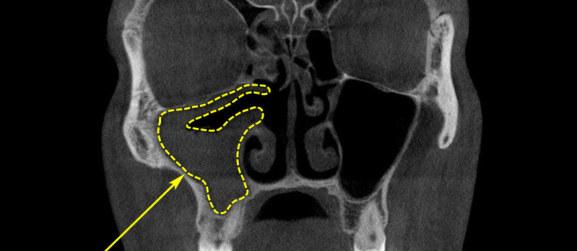

Грибковий гайморит або міцетома гайморової пазухи